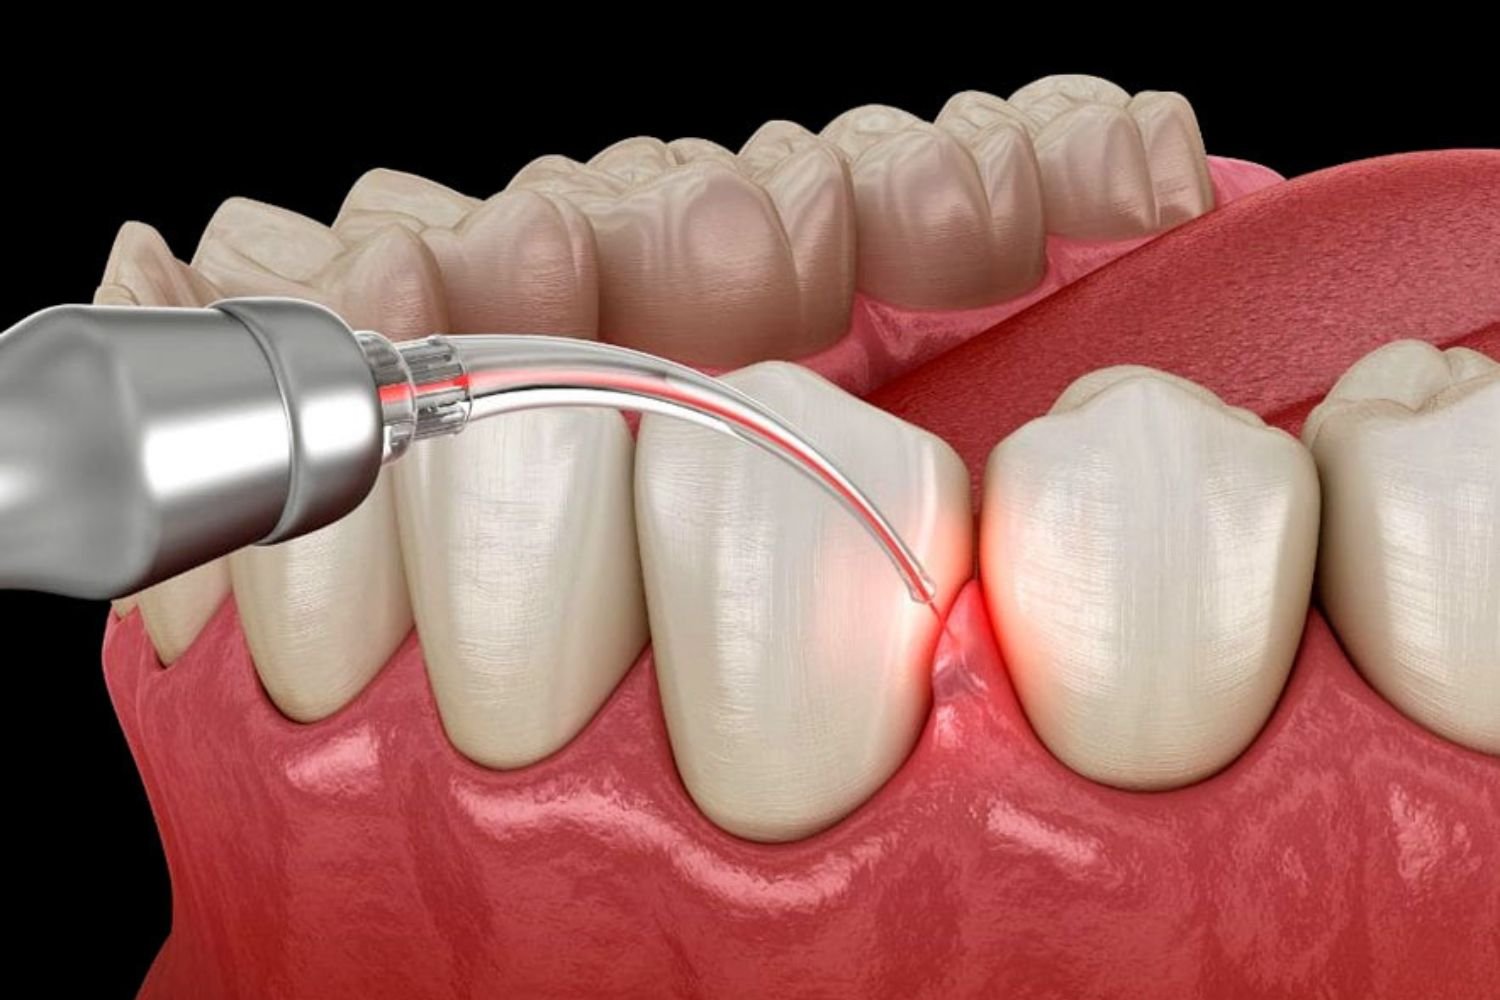

Gum Treatments

Advanced periodontal care effectively preventing gum disease and protecting long-term oral health naturally and safely.